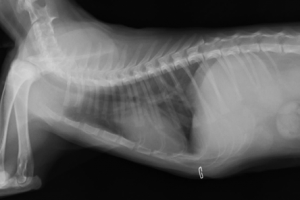

術後レントゲンです。心臓と横隔膜の位置が正常に戻り、呼吸状態も落ち着きました。術後5日目には退院となり、現在術後半年以上経ちますが、元気で過ごしています。横隔膜ヘルニアは交通事故などの外傷で起こすことがほとんどで、年齢とともに自然に発生することはまずありません。外出する猫ちゃんに多く、横隔膜ヘルニアになってしまったら呼吸状態が急激に悪くなり、死亡することが多いため早急な手術が必要です。予防策としては去勢、避妊などを早期に行い、外出を極力させないようにするしかありません。この猫ちゃんが助かってほんとによかったです(^o^)!